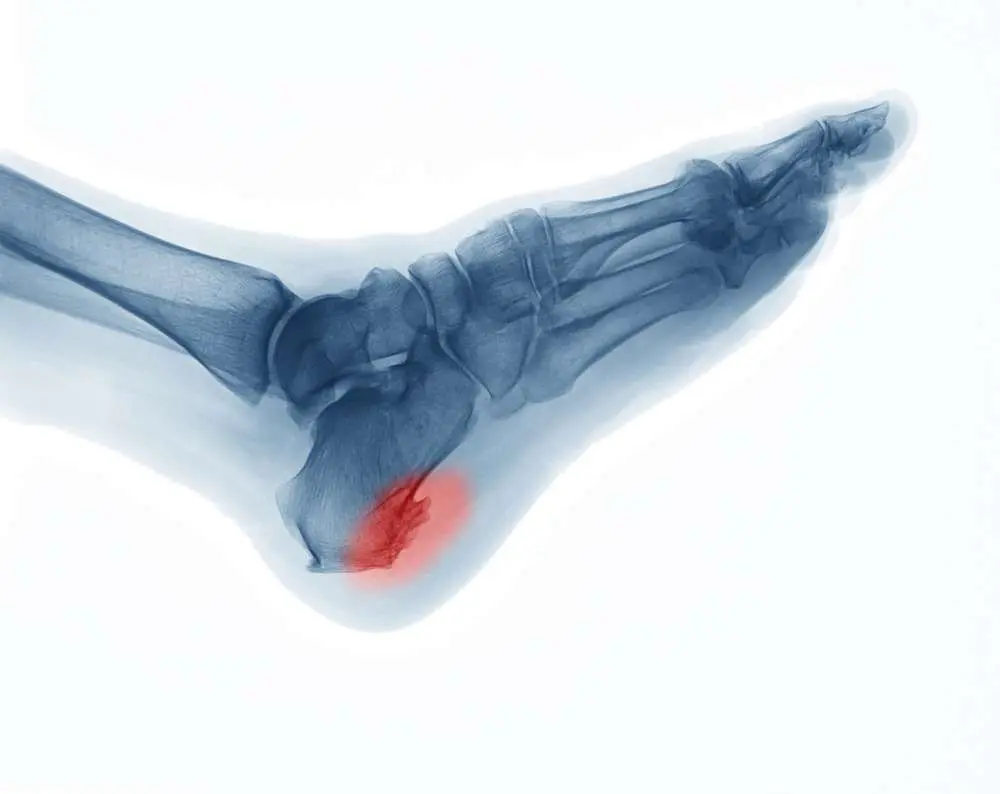

The heel spur, also called the calcaneal spur, usually manifests by affecting your plantar fascia.

This bony outgrowth from the heel bone is normally painless. However, if you play a sport that is heavy on your feet, such as running, your fascia will experience increased tension and can thus result in pain.